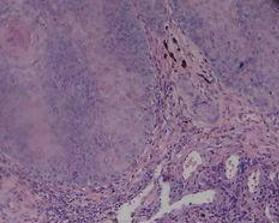

组织病理:大而深的活检为诊断本病所必需,其浅表部分一般与相似,表现为角化过度、角化不全和棘层肥厚。角质细胞分化良好,呈嗜酸性淡染、胞核小。呈宽索状侵袭,中央常有充以角蛋白的囊肿,大而呈珠状,向下增生压迫原束并将其挤向一侧。甚至在肿的深部亦无核的不典型性,个细胞角化和角珠。不过有些病例特口腔,偶尔也在生殖器肛门区和面处的状癌,最终也可表现核的非典型性和表皮失去极性而发展成真正的鳞状细胞癌。在罕见的情况下,口腔、生殖器和状癌,可见局部淋巴结转移。